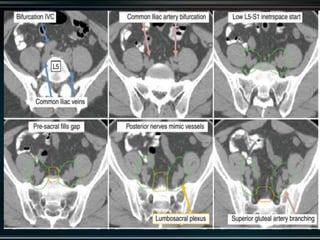

RTOG GU Consensus on pelvic LN CTV volumes:

 Commence contouring the pelvic CTV LN volumes at the L5/ S1

interspace (the level of the distal common iliac and proximal

presacral lymph nodes).

 Place a 7-mm margin around the iliac vessels connecting the

external and internal iliac contours on each slice, carving out

bowel, bladder, and bone.

 Contour presacral lymph nodes from S1 through S3, posterior

border being the anterior sacrum, and anterior border

approximately 10 mm anterior to the anterior sacral bone

carving out bowel, bladder, and bone.

 Stop external iliac CTV lymph node contours at the top of the

femoral heads (bony landmark for the inguinal ligament).

 Stop contours of the obturator CTV lymph nodes at the top of

the symphysis pubis.

RTOG GU Consensuson pelvic LN CTV volumes:  Commence contouring the pelvic CTV LN volumes at the L5/ S1 interspace (the level of the distal common iliac and proximal presacral lymph nodes).  Place a 7-mm margin around the iliac vessels connecting the external and internal iliac contours on each slice, carving out bowel, bladder, and bone.  Contour presacral lymph nodes from S1 through S3, posterior border being the anterior sacrum, and anterior border approximately 10 mm anterior to the anterior sacral bone carving out bowel, bladder, and bone.  Stop external iliac CTV lymph node contours at the top of the femoral heads (bony landmark for the inguinal ligament).  Stop contours of the obturator CTV lymph nodes at the top of the symphysis pubis.